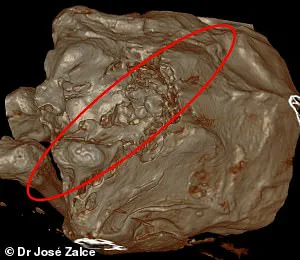

CT scans of one specimen, known as Maria—who measures five feet six inches—revealed bite marks, fractures, blood clots in tissue, and signs of internal trauma.

Images showed multiple fractures, including breaks in the scapula and ribs.

The team also described a zigzag-shaped wound with a broken pattern, suggesting that Maria may have fallen from a cliff and hit rocks during the fall.

This unusual injury, marked by irregular fractures and deep gouges, has led researchers to theorize a high-impact collision with jagged terrain.

This recurring mention of the injury underscores its significance, as it appears to be a critical piece of evidence in reconstructing the events leading to Maria’s death.

The wound’s placement along her lower back and legs has led some to theorize that she may have been in a defensive posture during the fall, attempting to shield herself from impact.

They noted that she was likely upright at the time of death, with her back pressed against a hard surface.

This posture, supported by the alignment of her spinal vertebrae and the distribution of pressure marks on her lower back, has led to theories that she may have been restrained or pinned in place before succumbing to her injuries.